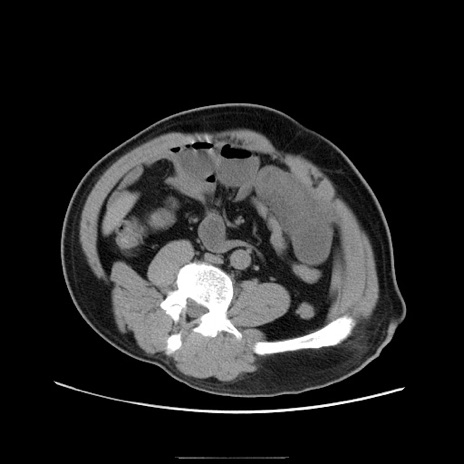

冠状断像

【症例】50歳代男性

【主訴】腹痛

【現病歴】AVMからの被殻出血のため回復期リハ病棟入院中。 本日午後3時頃急に下腹部痛が出現した。

【既往歴】AVM、被殻出血、虫垂炎、高血圧

【身体所見】意識晴明、左半身不全麻痺、会話の理解は良好、36.5°C、腹部:膨隆、全体に板状硬、下腹部正中に圧痛点あり、反跳痛-、筋性防御不明、右下腹部にope scar

【データ】WBC 9400、CRP 0.06